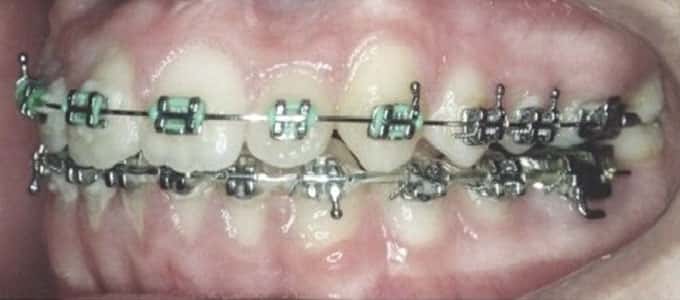

Aparatul fix metalic

Este cel mai des întâlnit tip de aparat, brackeții sunt fabricați din diverse aliaje metalice inoxidabile, așadar se văd cu ușurință. Cu toate acestea, aparatul fix metalic are o serie de avantaje demne de luat în considerare:

- durata de tratament mai scurtă

- brackeții sunt mai micuți si jenează mai puțin

- costurile sunt mai mici

- singurul dezavantaj al acestui tip de aparat este dat de aspectul estetic (brackeții sunt vizibili pe dinți)